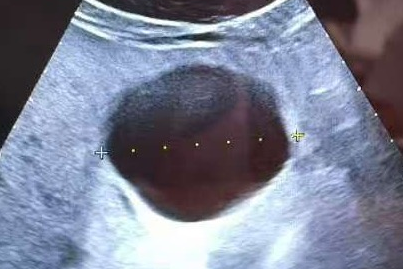

手术前,刘志龙教授通过详细问诊、全面体格检查及辅助检查结果分析,对患者病情做出了充分评估。他还亲自操作肝脏超声,精确评估肝囊肿状况。结果显示,患者肝囊肿直径超过5cm且伴有上腹不适,硬化治疗指征明确。刘教授随后耐心地与患者及家属沟通病情与手术方案,逐一解答疑问,使其紧张情绪得到极大缓解,患者及家属最终欣然同意接受治疗。

术前超声评估